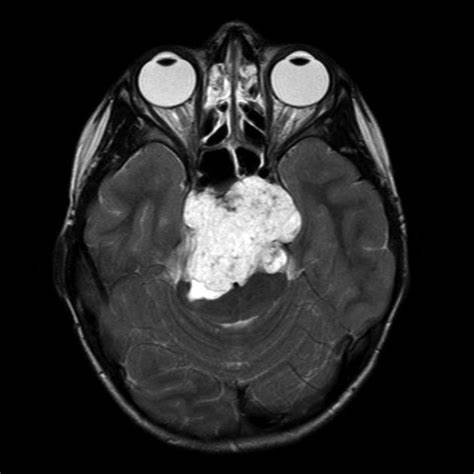

脊索瘤 是由胚胎脊索残留沿着神经轴的长度在发育活跃的部位产生的一种肿瘤。脊索瘤可能发生在脊柱的任何地方。它较常出现在尾骨附近(称为骶骨肿瘤)或脊柱与头骨(称为斜坡肿瘤...

脊索瘤 是一种少见的肿瘤,起源于脊索的残留--一种在胚胎发育过程中诱导和协调脊椎形成的结构。然而,在子宫的10周,脊索通常会退化,并且只在软骨盘的髓核中持续存在。 斜坡...

发病率只有百万分之一的 脊索瘤 一般在颅底中心线前方生长,具有分化低级别、生长缓慢、局部浸润和局部侵袭性的特点。由于解剖结构复杂,诊断和手术往往都很困难,而且手术后...